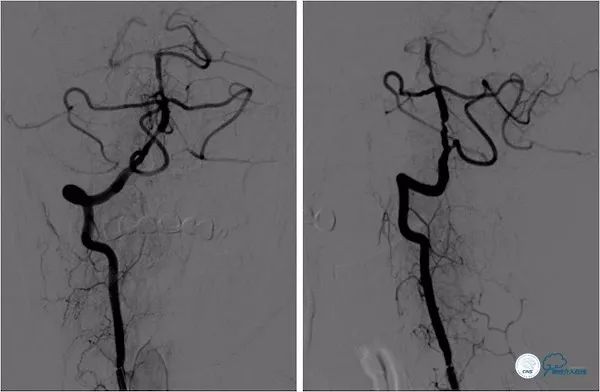

DSA:双侧颈动脉系统未见异常,双侧后交通动脉开放,右颈动脉造影可见基底动脉中上段显影。左椎动脉闭塞,右椎动脉V4段重度狭窄,基底动脉中段偏心重度狭窄(图5-8)。

图5

图6

图7

图8

治疗过程简述:全麻下右股动脉入路, 6F Guiding导引导管至右椎动脉V2段远端,术中造影示右椎动脉V4段重度狭窄,基底动脉中段中重度狭窄(图11)。